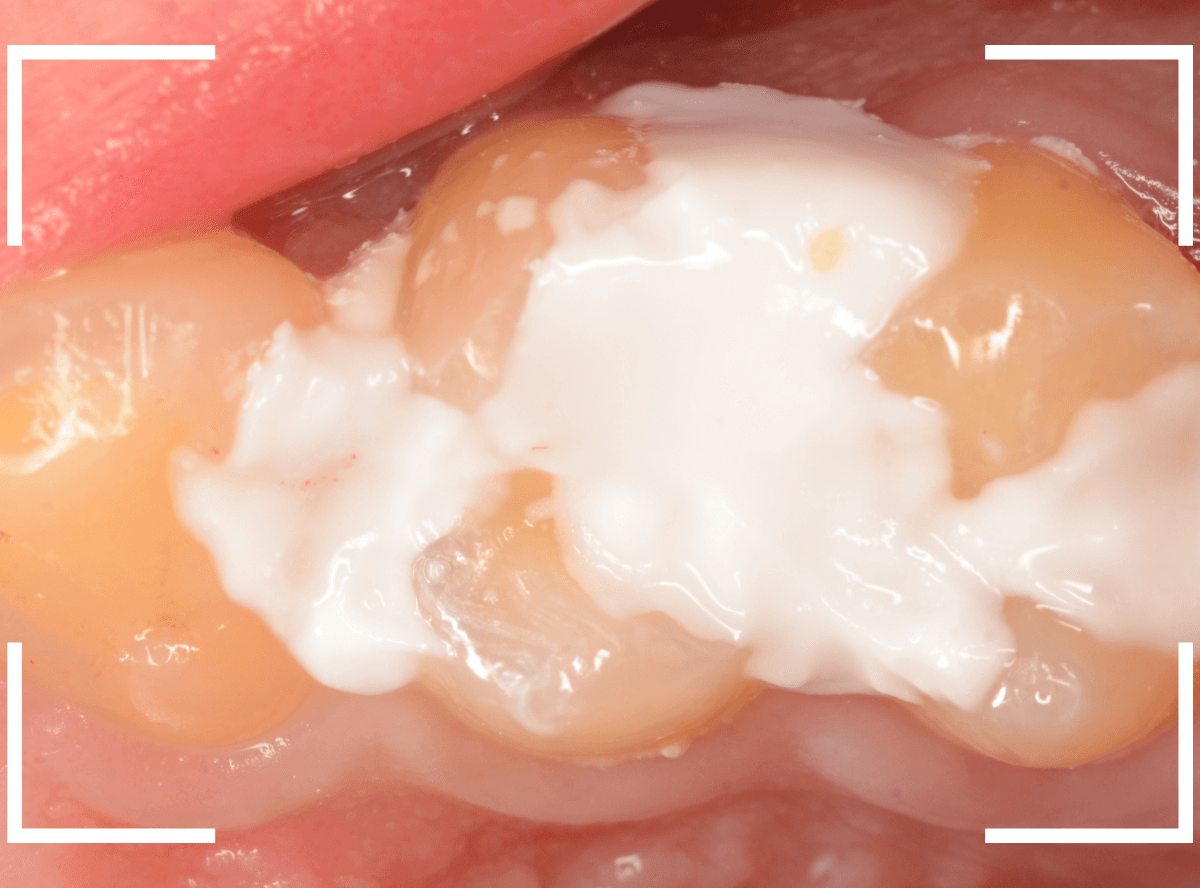

Case.2 症状がないけど、神経が見えるほどの虫歯!

こちらも別の歯の治療を目的に受診された方です。

特に症状もないため、本人には全く自覚はありませんが、一目見てわかるほど歯と歯の間に大きな虫歯があります。

治療をすると、やはり大きな虫歯が出てきました。

まだまだ虫歯は深いです。

かなり大きく削りましたが、まだ虫歯が残っているのがわかります(赤く染まっている部分)。

慎重に虫歯を除去し、神経ギリギリのところで虫歯をくいとめました。

しかし、手前の歯をよく見ると、神経がうすく透けて見える状態ですので、本当にギリギリです。

このような深い状態の虫歯でも、症状がなく、治療後に痛み出す事もあります。

今回もお薬をつめて、お痛みが出ないかしばらく経過観察となりました。